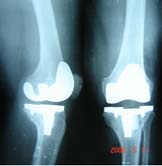

(二)X線檢查

關節周圍軟組織腫脹影,骨質疏鬆,以後關節間隙變窄,骨盾破壞,反應發現有質增生。晚期關節呈纖維性或骨性融合,死骨形成,關節脫位或間脫位。X線檢查時,在早期由於關節液增加而關節囊腫脹,間隙增寬,骨端逐漸有脫鈣現象。如關節面軟骨有破壞,則關節間隙變窄。有時可講發骨骺滑脫或病理性脫位。較晚期,關節面下骨質呈反應性增生,骨質硬化,密度增加。最後關節軟骨完全溶解,關節間隙消失,呈骨性或纖維性強直,或餅發病理性脫位。其X線表現為:

1. 早期關節內有化膿性炎症時,關節周圍軟組織常有充血及水腫,表現為軟組織厚於健側,層次不清。關節囊因關節內積液而膨脹,脂肪層被推移呈弧形。偶爾可見關節間隙輕微增寬,應與健側對照,才不會漏診。

2.關節間隙狹窄化膿性細菌進入關節後首先引起的滑膜炎。滲出液內含有大量中性白細胞。白細胞死亡後所釋放出的大量溶蛋白酶、很快地溶解關節軟骨。根據關節軟骨被破壞的程度,常於發病後短期內出現關節間隙狹窄,甚至完全消失。

3.關節面改變關節軟骨被破壞後,即可進一步破壞軟骨下骨質。最早出現在關節面的相互接觸部分,即負重部分。表現為關節面模糊和不規則。繼而形成較大的破壞區,形成死骨。由於機體的修復作用,破壞區周圍因骨質增生而密度增大,關節邊緣有唇樣骨質增生。當骨小梁貫穿關節間隙以聯接兩側骨關節面時稱之骨性強直。

4.關節軟骨及骨質破壞嚴重時可引起脫位或半脫位一般青少年和成人,常因關節軟骨破壞形成骨性強宜,而兒童多發生骨端的破壞,吸收,引起病理性脫位。